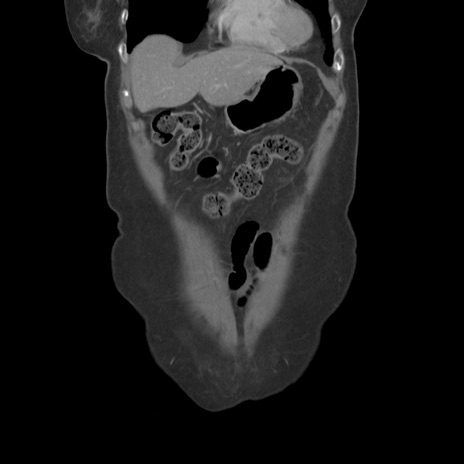

症例19(冠状断像)

横断像